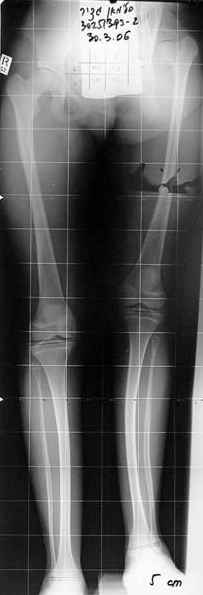

Moghno i tak kak sdelali my: pelvic support + tibial and equinus correction .

Слайд 1